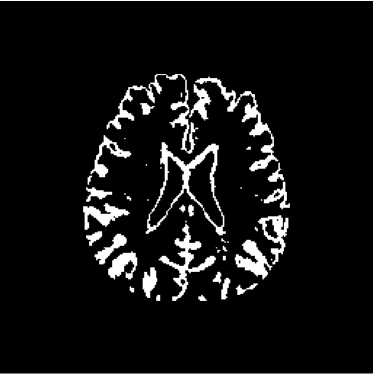

Figure 28 shows 13th slice of classification result obtained by the use of the objective dialectical classifier. Figure 29 exhibits 13th slice of classification result after performing post-labeling, whilst figure 30 shows the entire volume generated by ODC classification.

The training process of ODC algorithm resulted in 6 classes. These classes were reduced to 4 after manual post-labeling, merging 3 classes out of brain region, namely image background, noise and cranial box. The post-labeling is manual because all 3 cited regions are statistically different and, consequently, they are merged due to our interest in classes more related to the brain regions. On figure 29 it is possible to notice that ODC was able to distinguish white matter from the gray matter present in the interface between liquor and white matter.

Figure 29: 13th slice of objective dialectical classification after post-labeling

Observing figure 34 indicating the detection of gray matter by the objective dialectical classifier, we can perceive the significative reduction of gray matter in brain frontal lobule, better seen in superior part of image. This lobule is directly related with the reduction of recent memory.